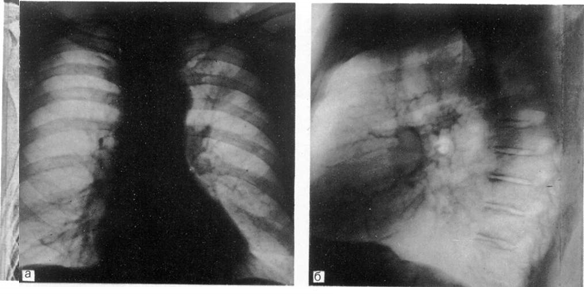

Рис. 3.

Рак верхней доли левого легкого.

а — прямая рентгенограмма: б — боковая рентгенограмма.